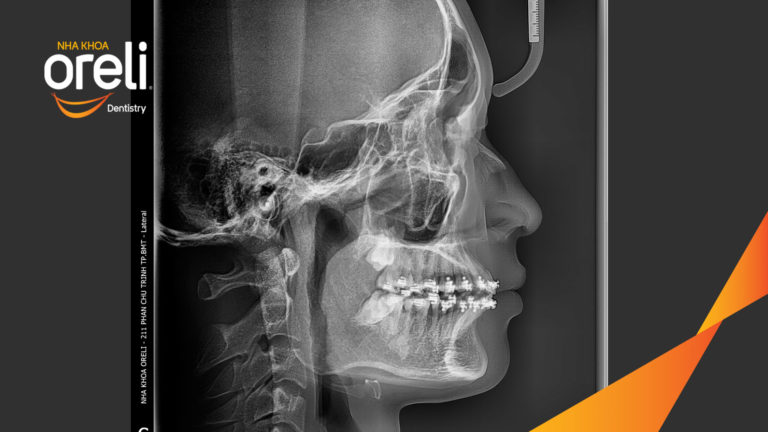

Ca niềng chỉnh chen chúc sai khớp cắn hạng 3 móm nhẹ – Kết quả thực tế ở Oreli Niềng răngChen chúcMóm Xem thêm